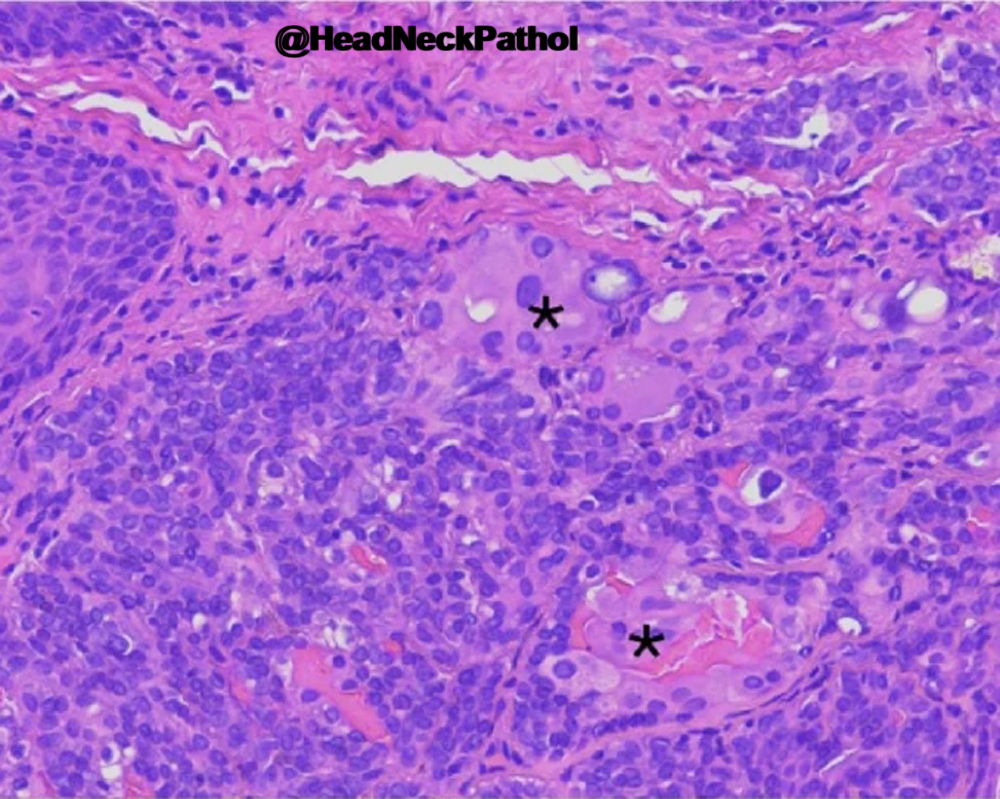

Characterization of CD8 + & CD68 + Microenvironment & PDL1 Expression in HPV-related Multiphenotypic Sinonasal Carcinoma

Silva de Araújo, Gonçalves de Paiva, Lima Fernandes, et al.